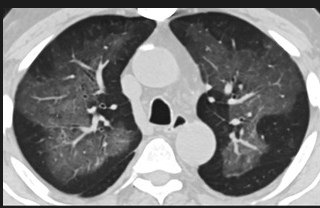

怎么“中度可疑”呢?这些专家表示,这5位患者的肺部CT都具备新冠肺炎CT的影像特征,比如肺部出现磨玻璃的影像,磨玻璃主要分布在双下肺靠近外周,出现铺路石征、严重的表现为双肺弥漫性多发实变。同时,其病程转归和临床特征也与新冠肺炎相似。

以下面这4张图涉及的这个美国“电子烟”病人为例,专家不是仅仅通过一张影片做判断的,而是通过这4张涵盖了这名病例肺部多天变化情况的影片进行的研判,认为该病例的病程进展跟新冠更为相似。